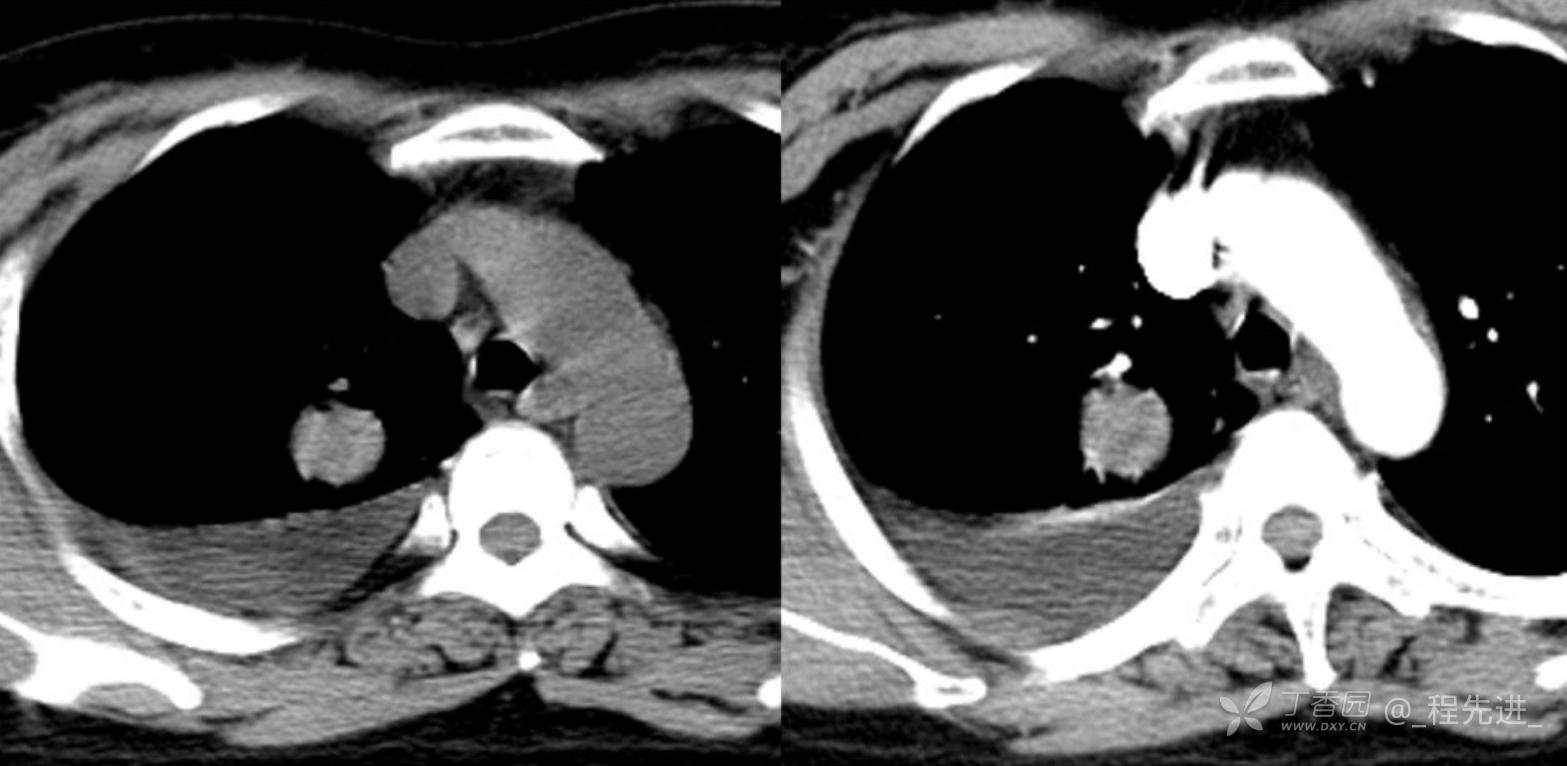

简要病史:乏力、纳差20余天,皮肤巩膜黄染半月偶有咳嗽,咳白痰,全身皮肤巩膜黄染。无咯血,无明显胸闷、胸痛,无明显气促,无发热及盗汗。精神欠佳,纳差,睡眠一般,二便正常